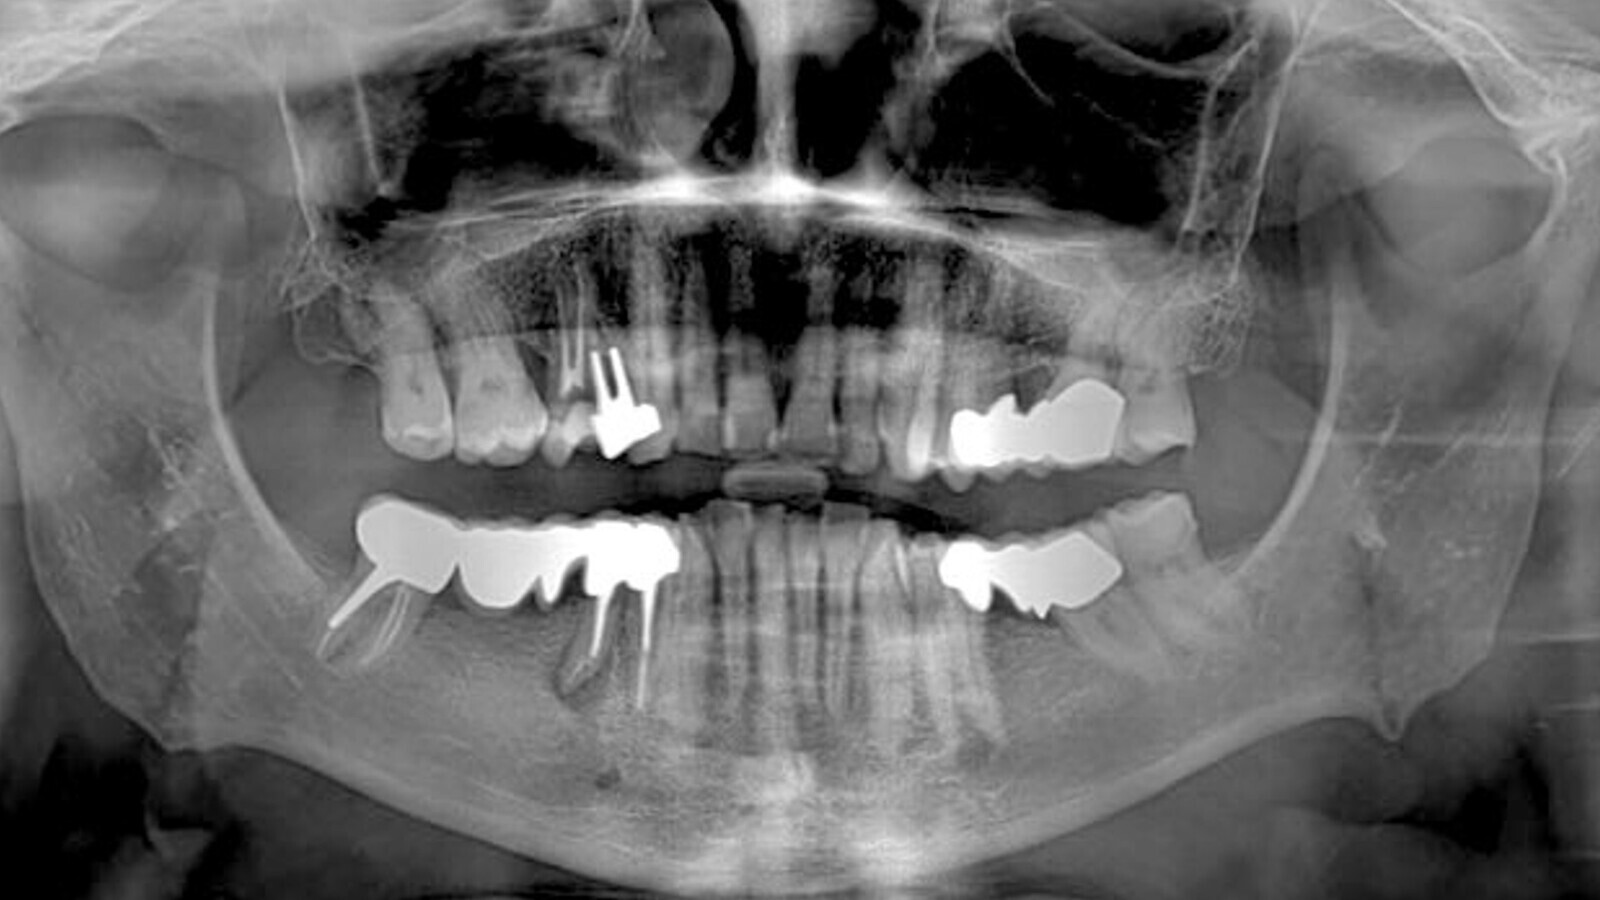

Caso clínico de una mujer de 58 años de edad, en buen estado de salud, que acudió al cirujano para solicitar una rehabilitación implantológica a raíz de la excesiva movilidad y migración apical del puente metal-cerámico en los dientes 44-46. Tras la investigación clínica y radiográfica (Fig. 1), se observó un déficit óseo horizontal. Por lo tanto, se realizó un ROG horizontal y la colocación simultánea de implantes en las posiciones 44 y 46.

Fig. 1. Ortopantomografía inicial: se observa un puente metal-cerámico en las posiciones 44-45-46 con movilidad del pilar.